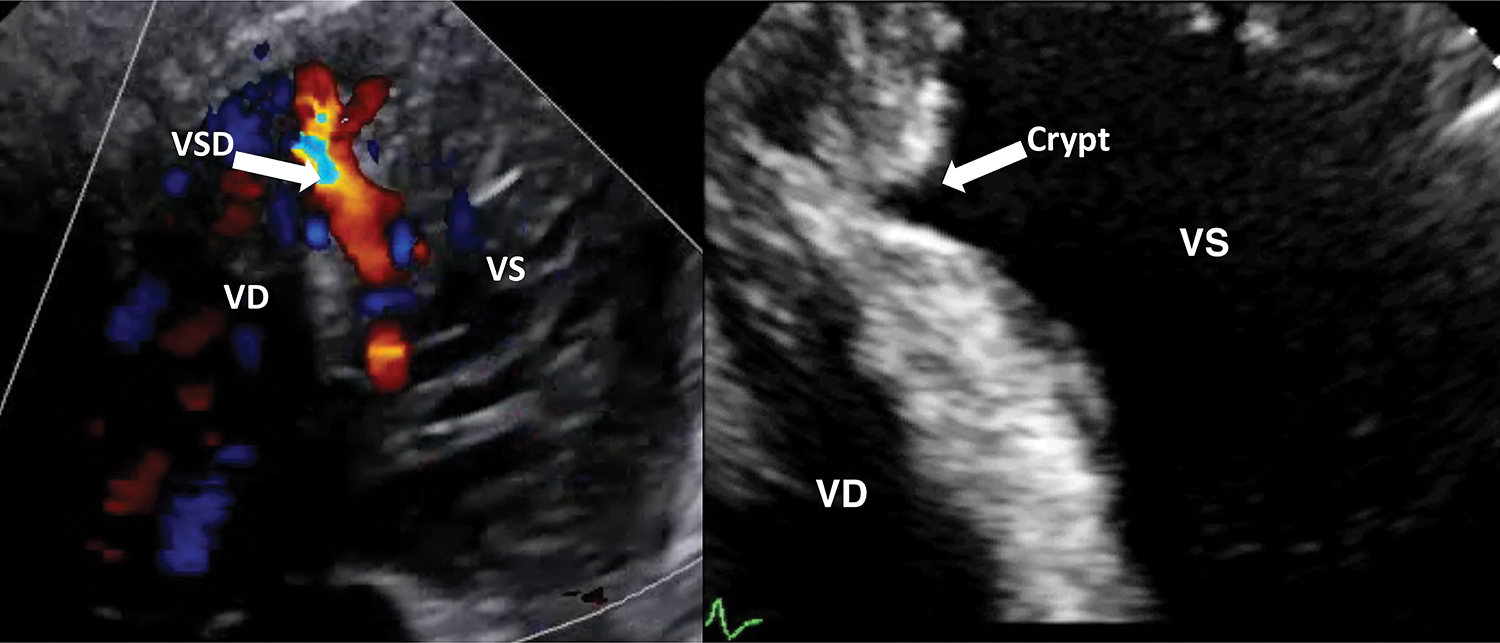

The main finding of this study is that residual crypts of the interventricular septum may represent the possible evolution of a spontaneously closing VSD (Fig. 1). This happened in 6.4% of our population of 314 trabecular VSD patients prospectively followed up for a long period (1 to 23 years, median 12 years). We have previously published a large case-series VSD documenting a very high incidence of spontaneous closure, especially among muscular ones, with different frequency, timing and pathophysiology [4].

Figure 1: A case of spontaneous closure evolved in a septal crypt formation